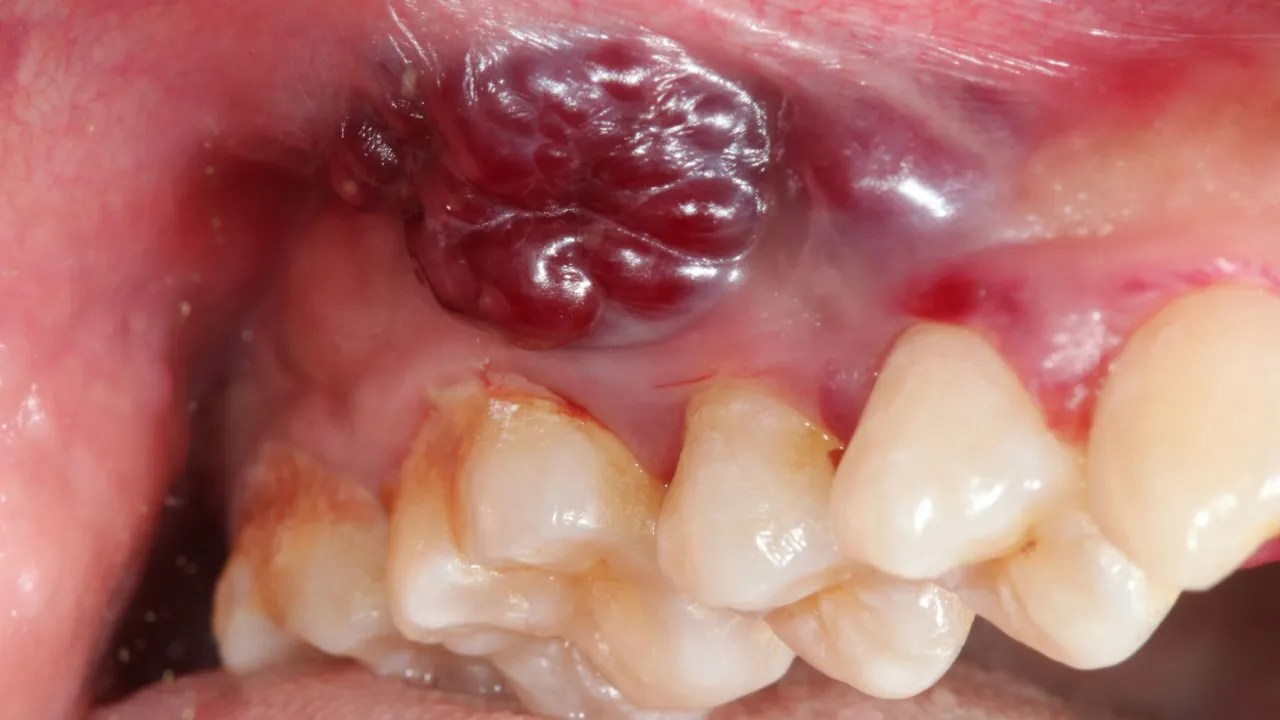

Zakażenie wirusem brodawczaka ludzkiego (HPV) w jamie ustnej może manifestować się w postaci różnych zmian, które są często widoczne gołym okiem. Najczęstsze objawy to brodawki, kłykciny oraz kurzajki, które mogą pojawiać się jako niewielkie, brodawkowate wypukłości. Zmiany te występują na języku, wewnętrznej stronie policzków, dziąsłach lub wargach. Ich kolor może być różowy, czerwonawy, a czasami nawet blady lub białawe.

Te objawy mogą przybierać formę małych, mięsistych guzków o nierównej powierzchni, przypominającej kalafior. U dorosłych, w zależności od wielkości zmian, mogą występować dodatkowe objawy, takie jak ból lub dyskomfort podczas jedzenia i mówienia. Warto zwrócić uwagę na te zmiany, ponieważ mogą one prowadzić do poważniejszych problemów zdrowotnych, szczególnie u osób z obniżoną odpornością.

Brodawki i kłykciny - jak wyglądają i gdzie się pojawiają

Brodawki i kłykciny to jedne z najczęstszych objawów zakażenia HPV w jamie ustnej. Brodawki mogą mieć różne kształty i rozmiary, ale zazwyczaj są małe, mięsiste i mają nierówną powierzchnię. Mogą być zlokalizowane na języku, wargach, dziąsłach oraz wewnętrznej stronie policzków. Z kolei kłykciny to zmiany, które często przypominają kalafior i mogą występować w grupach, co sprawia, że są bardziej widoczne.

Zmiany przedrakowe związane z HPV mogą przybierać różne formy, ale zazwyczaj są to zmiany o nieregularnej powierzchni, które mogą być różowe lub białawe. Mogą one występować jako małe grudki lub brodawki, które nie ustępują z czasem. Ważne jest, aby zwracać uwagę na wszelkie zmiany, które są trwałe lub rosnące. Wczesne wykrycie takich zmian jest kluczowe dla skutecznego leczenia i zmniejszenia ryzyka rozwoju nowotworu. Regularne wizyty u lekarza oraz samobadanie jamy ustnej mogą pomóc w identyfikacji tych niepokojących zmian.